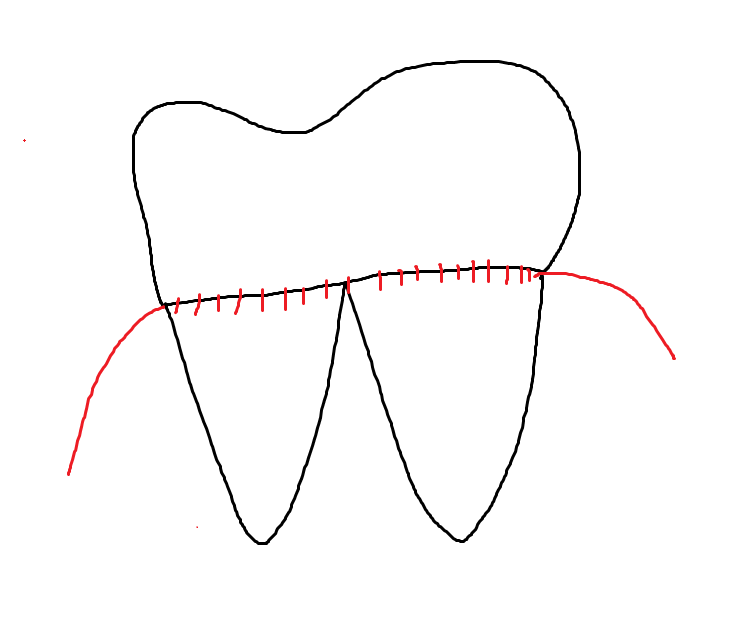

오늘의 환자분은 치아 뿌리 충치가 원인입니다.

서서히 치아를 파먹으면서 뿌리가 부러졌네요~

치과 용어로는

"치근 우식증"이라 표현하는데요.

치아 뿌리 충치가 파절을 유발했기에

씹을 때 시큰하다거나...

욱신한 느낌~